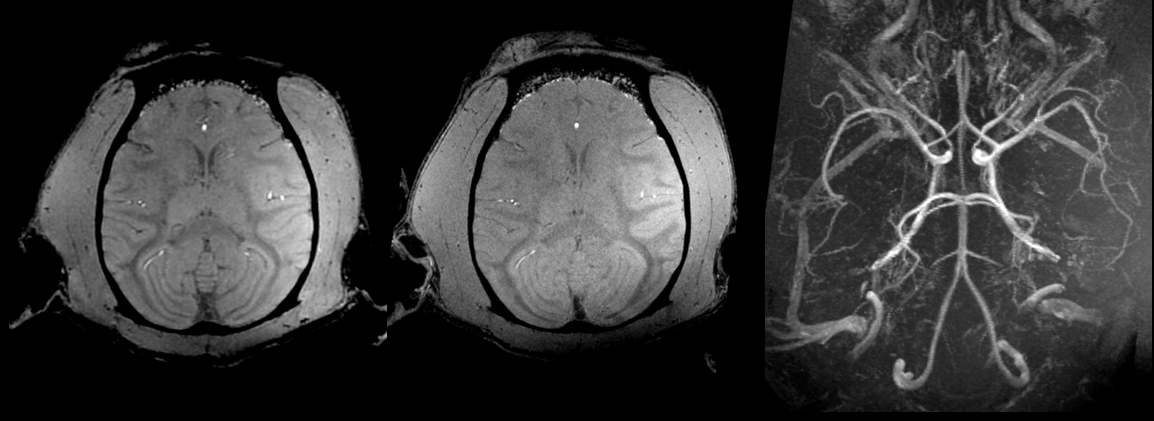

Figure 2 illustrates the quality of the 300-µm and 500-µm isotropic raw GRE and Maximum Intensity Projection images (MIP) of the same images. Figure 3 displays 800-µm T1-weighted MPRAGE images

In vivo MRI data acquired in one macaca rhesus at 11.7 T with 3D MPRAGE sequences in pCP mode. The images were reconstructed from left to right respectively in sagittal, coronal and transversal planes with 3D MPR out of 800um isotropic acquisitions. The images reveals classic T1 weighted contrast but also strong B0 artefact on the top of the head because of poor shimming and signal losses mainly in the back of the head probably due to the inversion pulse operating out of the adiabaticity regime.